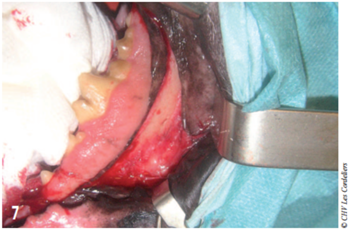

Des champs stériles ont été placés sous la tête de l’animal puis autour de la bouche a la jonction cutanéomuqueuse. Un aide opératoire rétractait la commissure des lèvres avec des écarteurs de Faraboeuf ce qui donnait un accès suffisant à la mandibule sans incision des babines (photo 7).

Photo 7 : La rétraction des babines par un assistant permet un accès à la partie caudale de la mandibule. La gencive a été incisée et élevée de l’os.